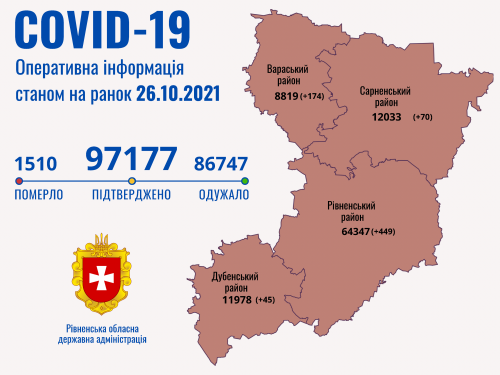

Пів тисячі - у важкому стані, 9 жителів Рівненщини померли за добу від коронавірусу